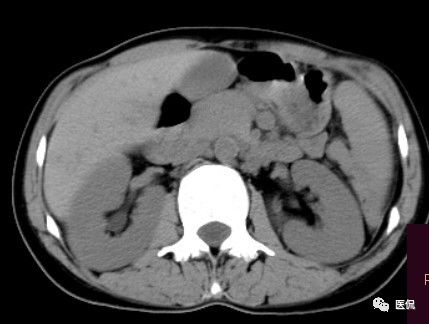

腹腔内残留的纱布在人体内引起渗出或液化坏死并纤维包裹形成异物性脓肿(纱布瘤)。纱布瘤的影像特点:圆形或卵圆形肿块,较大,有完整包膜,薄壁,较少的情况下为厚壁,边界较完整,增强后薄膜可以持续强化。不同时期的纱布瘤可以有不同表现:早期(10个月或半年内)多表现为蜂窝状;2~5年内一般表现为囊性飘带状;10~20年之后则为实性软组织密度,包膜钙化呈钙化网状结构。手术过程中残留在人体内的医用纱布所形成的肿瘤样病变。

纱布团遗留腹腔后,首先由大网膜及邻近肠管将其紧密粘连并包裹,自肠管与纱布团粘连处开始逐渐向周围扩展产生纤维结缔组织包膜直至完全包住纱布团,该包膜血管丰富,充血明显,随时间延长逐渐向纱布团网眼内生长,使包膜逐渐增厚。机体还通过在包膜内产生大量异物巨细胞来围歼异物纱线,使包膜内侧形成脓肿。当包膜完全形成后,肠管与纱布团的粘连变的疏松,此时纱布团具有了一定的活动度。

腹腔内遗留纱布团的影像学表现,以B超较具特征性,其主要表现为:腹腔或盆腔内特殊率减的黑色包块,后方伴有扇形衰减的声影,上窄下宽,好似一“黑色大布”,早期包块内含有不规则光团或光点,随时间延长有缩小或消失,为纱布团内气体。CT的优势在于早期常表现为软组织密度的肿块,其内可见多少不等的气泡,随时间的延长气泡逐渐被吸收减少至消失,增强扫描可见包膜不同程度强化而内容物无强化。熟悉其影像学表现,可在术前作出明确诊断。